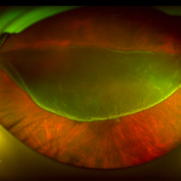

Post Injection Endophthalmitis

Nov 21 2020 by Suhwan Lee, MD

Stillcut image of eye with post-intravitreal injection endophthalmitis during emergency vitrectomy. The patient received intravitreal injection for neovascular age-related macular degeneration 2 days ago. Image that was taken after anterior chamber irrigation and core vitrectomy showed multiple retinal hemorrhage and whitening of retinal vessels.

Photographer: Suhwan Lee, MD

Imaging device: Stillcut image of surgical video (Lumera 700 )